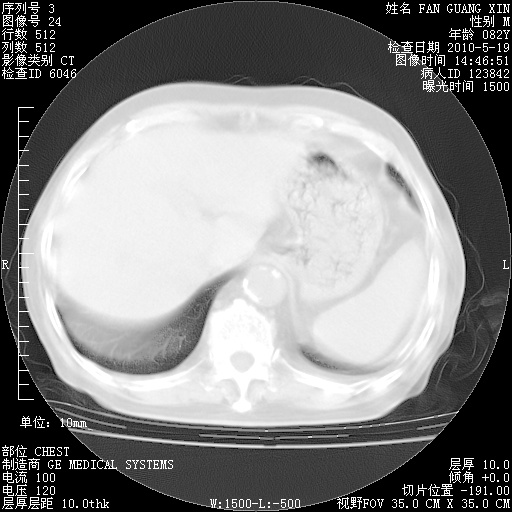

可改为口服强的松40-50mg/d治疗,若病情仍稳定,胸部阴影不再吸收可逐渐减量